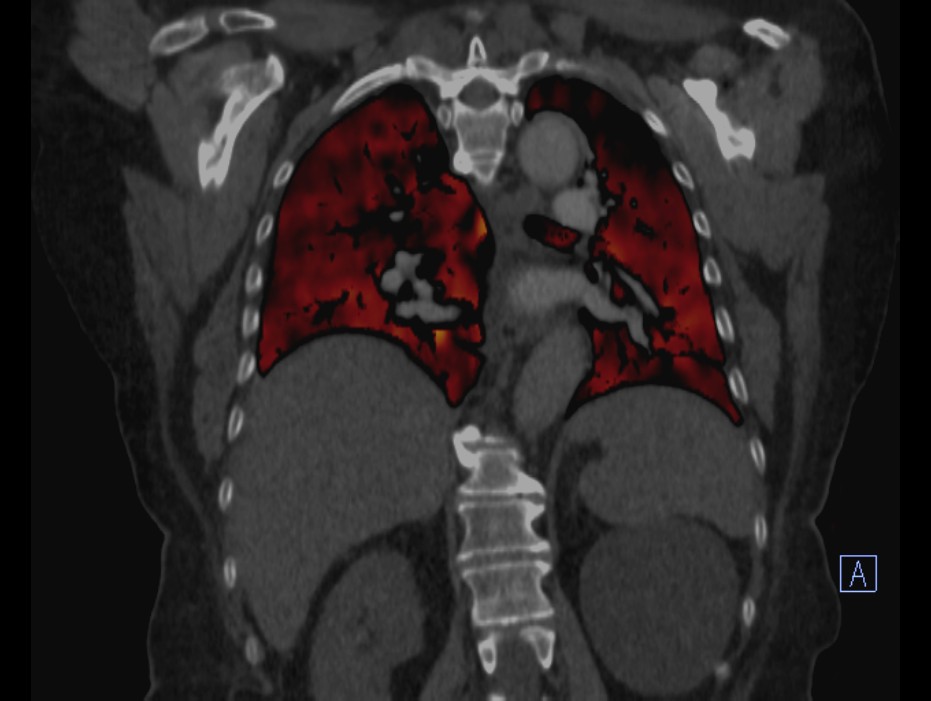

Sistemin bu özelliği sayesinde, Başkent Üniversitesi Adana Hastanesi bünyesindeki yeni versiyon Dual-Enerji bilgisayarlı tomografi cihazında da normalde diğer merkezlerde kullanılan kontrast maddenin yaklaşık 1/3 miktarı ile son derece başarılı Akciğer damar görüntülemesi (Pulmoner  Anjiografi) ve aynı seansta akciğerlerin kanlanma düzeyini gösteren “Perfüzyon” değerlendirmesi de yapılabilmektedir. Bu sayede merkezimizde, başta böbrek sorunu olan hastalar olmak üzere birçok hasta grubunun kontrast madde kaynaklı böbrek hasarı (nefrotoksisite) olmadan akciğer damar yatağı (Pulmoner  Anjiografi) görüntülemesi yapılabilmektedir.

OLGU 1.

Sağ üst lobta Kronik PTE perfüzyon defekti gözlenmektedir.